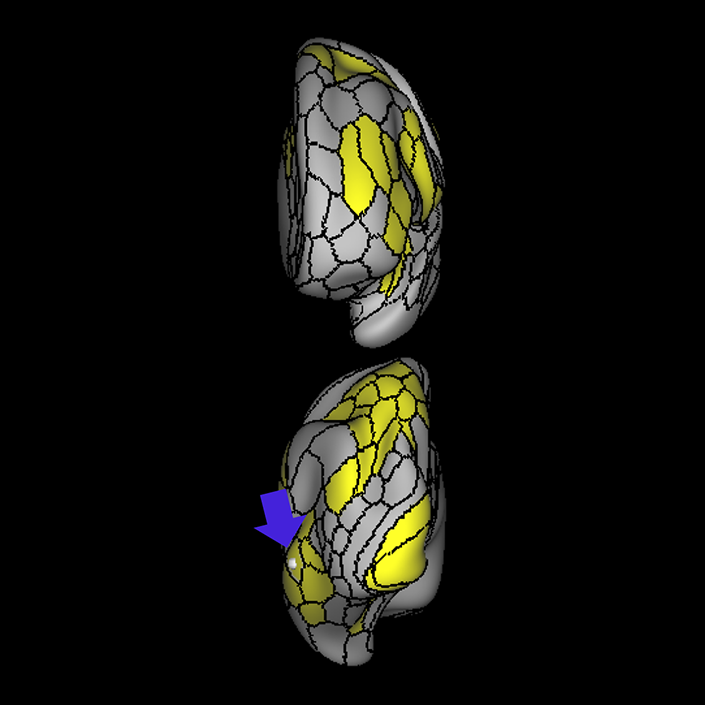

ᐅ SummaryArea 44: part of the inferior frontal gyrus of the lateral frontal lobe. Translates abstract and intentional information in the prefrontal cortex to more detailed representations to help guide the production of verbal and manual actions. In addition to its known association with Broca's area, is sometimes represented as part of Broca's complex ᐅ Where is it?Area 44 is at the posterior most part of the inferior frontal gyrus. It is the anterior bank of pars opercularis of the IFG. ᐅ What are its borders?Area 44 borders area 45 anteriorly and area 6r posteriorly. Area 8C is its medial border and its inferior border is wedged between then upper borders of Areas 6R and 6V. Its superior edge borders IFSp and IFJa. Its opercular surface is FOP4. ᐅ What are its functional connections?Area 44 demonstrates functional connectivity to areas SFL, IFSp, IFJa, 45, 47s, 47L, 9a, 9m, 8AV, 8BL and 8C in the dorsolateral frontal lobe, area 8BM in the medial frontal lobe, area 55b in the premotor areas, areas FOP5, AVI and PSL in the insula- opercular region, areas TGd, STSdp and STSvp in the temporal lobe, areas PFm, and PGi in the inferior parietal lobe, and no areas in the medial parietal lobe. ᐅ What are its white matter connections?Area 44 is structurally connected to the arcuate/SLF and the FAT. Connections with the arcuate/SLF project posteriorly and wrap around the Sylvian fissure to the middle temporal gyrus to end at TE1a and TE1m. There are also projections from the arcuate/SLF before it terminates to parcellations A5 and STSdp. The majority of the inferior connections of the frontal aslant tract end at 44, the tract is connected superiorly to superior frontal gyrus parcellations SFL, 6ma and s6-8. Local short association bundles are connected with 45 and 8C. White matter tracts from 44 in the right hemisphere have less consistent connections with the arcuate/SLF. ᐅ What is known about its function?Area 44 translates abstract and intentional information in the prefrontal cortex to more detailed representations to help guide the production of verbal and manual actions. Area 44, in addition to its known association with Broca's area, is sometimes represented as part of "Broca's complex", including Brodmann Areas 45, 46, 47 and the mesial supplementary motor area of 6, which contribute to a frontal-subcortical circuit. The right pars opercularis has also been implicated in cognitive inhibition in the overall context of working memory. |

A: lateral-medial

B: anterior-posterior

C: superior-inferior

DTI image |